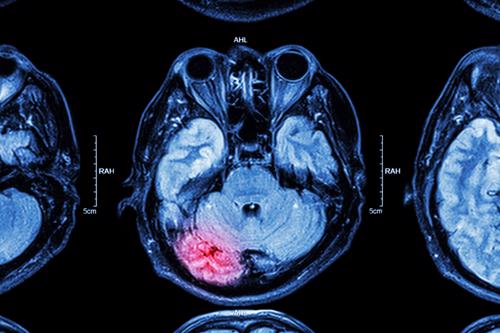

A traumatic brain injury is a severe and devastating injury resulting from trauma to the head.

Traumatic brain injuries can be classified into various groups depending on what caused them.